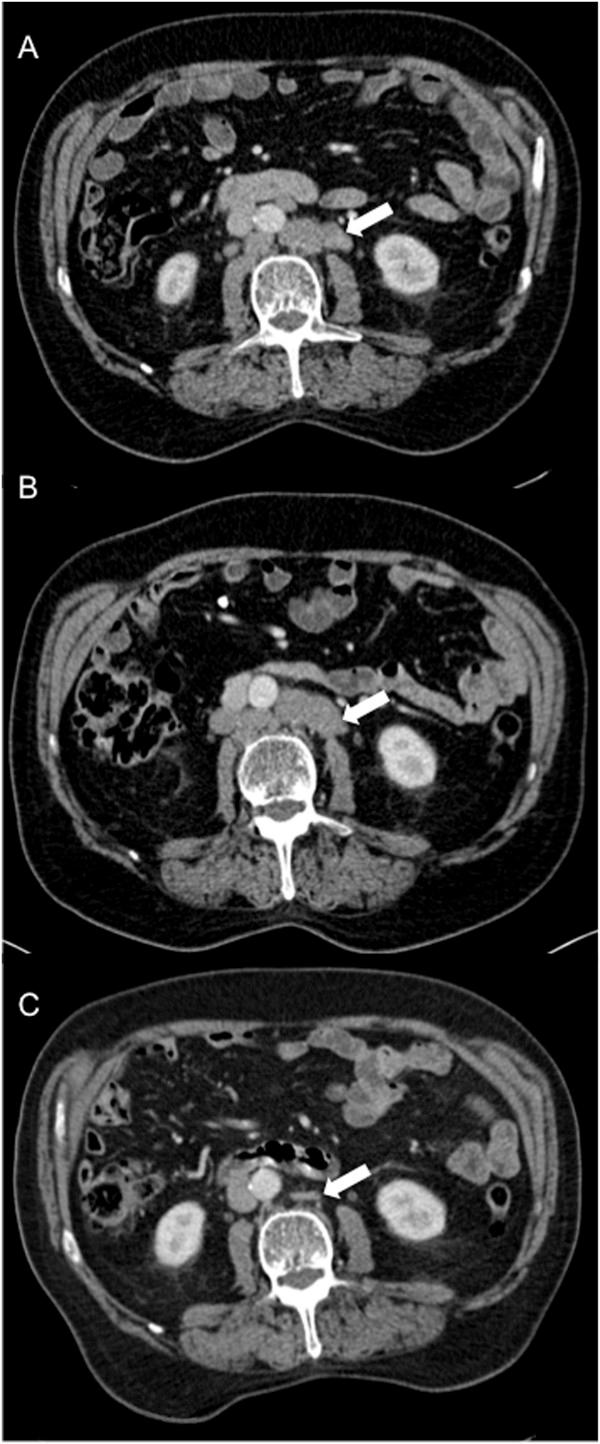

We present a case of a 72-year-old White man of British origin with metastatic castrate-resistant prostate cancer with bulky lymphadenopathy and a serum prostate-specific antigen of 295 μg/L. He received treatment with docetaxel chemotherapy plus prednisolone, but received just 3 cycles before treatment was stopped due to toxicity and lack of response (prostate-specific antigen was 276 μg/L 4 weeks after the last dose and there was a confirmed stable appearance on computed tomography scan). Unexpectedly, at follow-up 4 months later, the patient was clinically better; his prostate-specific antigen had dramatically improved to 4.1 μg/L and a re-staging computed tomography scan revealed complete resolution of his bulky lymphadenopathy. At the time, he was receiving a luteinising hormone-releasing hormone analogue but no other disease-modulating treatment. He remains well and asymptomatic, with his most recent serum prostate-specific antigen measuring 0.14 μg/L, 18 months after last receiving chemotherapy.

我们报告一例72岁、祖籍英国的白人男性,患有转移性去势抵抗性前列腺癌,伴有巨大淋巴结病,血清前列腺特异性抗原为295μg/L。他接受了多西他赛化疗加泼尼松龙治疗,但由于毒性反应和缺乏疗效(最后一剂后4周前列腺特异性抗原为276μg/L,计算机断层扫描显示外观稳定),仅接受了3个周期的治疗就停止了。出乎意料的是,4个月后的随访中,患者临床症状改善;他的前列腺特异性抗原显著改善至4.1μg/L,重新分期的计算机断层扫描显示其巨大淋巴结病完全消退。当时,他正在接受促黄体生成素释放激素类似物治疗,但未接受其他疾病调节治疗。在最后一次接受化疗18个月后,他仍然状况良好且无症状,其最近的血清前列腺特异性抗原测量值为0.14μg/L。